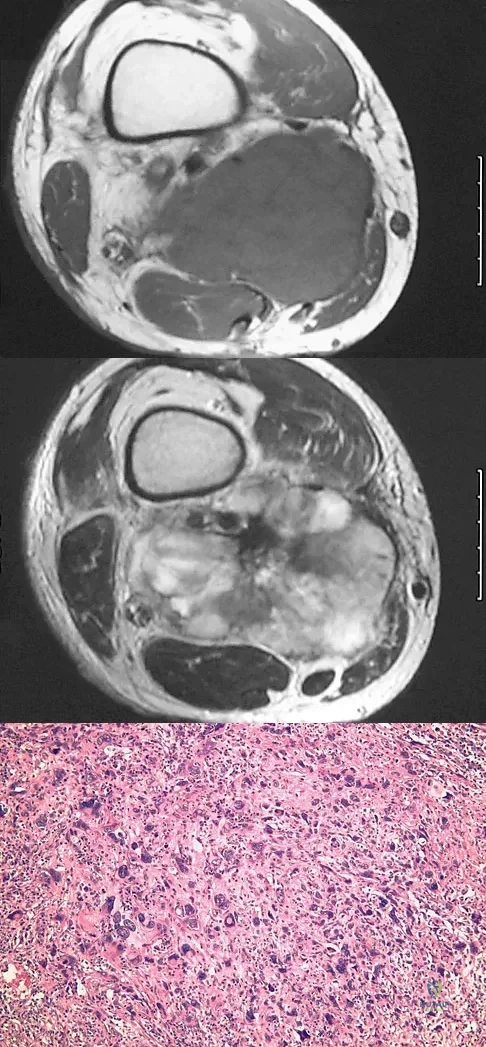

A 37-year-old man pulled his hamstring playing softball 3 weeks ago. The patient had not noted any mass prior to his injury. MRI scans of the posterior thigh are shown in Figures 4a and 4b. Figure 4c shows the biopsy specimen from a needle biopsy. What is the most likely diagnosis?

Explanation

A 16-year-old boy has had left knee pain and swelling after sustaining a minor twisting injury while playing basketball 2 weeks ago. Figures 5a through 5e show the radiograph, MRI scans, and biopsy specimens. What is the most likely diagnosis?

Explanation